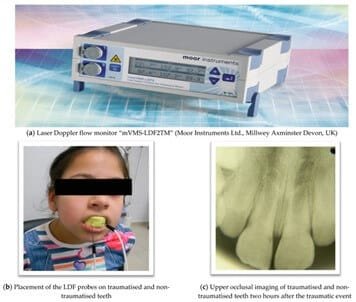

Laser Doppler Flowmetry

- Purpose: measures blood flow within the pulp for more precise vitality assessment.

- Procedure: laser directed at tooth; changes in blood flow recorded.

- Interpretation: low/absent flow → necrosis; normal flow → healthy pulp.

- Limitations: less commonly used due to complexity and cost.